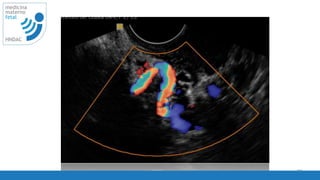

disminuir

ganancia 2D

ISUOG - Guidelines 2013